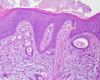

Case presentation: We here describe an uncommon case of a hard palate mucosa and gingival metastasis from gastric carcinoma that was originally diagnosed as a periodontal disease. Histopathological examination of a biopsy of the lesion revealed a signet-ring cell carcinoma, and a subsequent biopsy of an ulcerated stomach lesion showed a poorly differentiated gastric carcinoma. The patient underwent gastric resection but died of heart failure on the tenth postoperative day; a post-mortem examination revealed a residual bilateral ovarian infiltration by gastric carcinoma (Krukenberg's tumor).